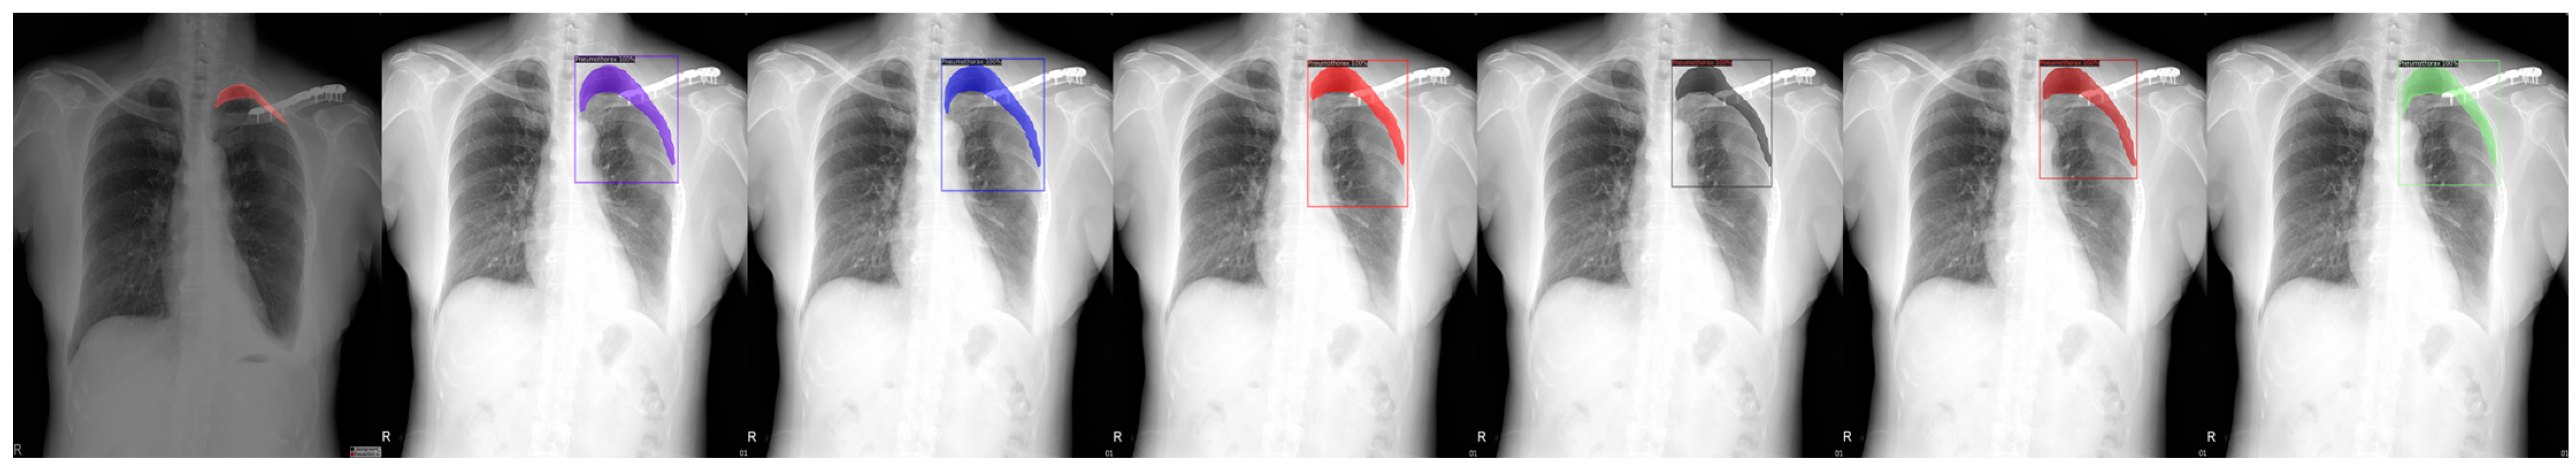

Figure 3.

From left to right: Ground Truth, ResNet50 (COCO), ResNet101 (COCO), ResNeXt101 (COCO), ResNet50 (LVIS), ResNet101 (LVIS), and ResNeXt101 (LVIS). This patient had pneumothorax in their right chest.

We chose a few examples to demonstrate the capabilities of various models. These images consisted of X-ray images of pneumothorax patients with different areas of disease inflicted. The inclusion of multiple positions and areas in the figures lets us observe the possible outcomes and the differences between the models. In Figure 3 and Figure 6, the patients had pneumothorax on the right side of their chest, with the patient in Figure 6 only affecting the top part, while the patient in Figure 3 had pneumothorax on the outside wall of their right lung. In Figure 4, Figure 5 and Figure 7, the patients had pneumothorax in the left side of their chest, while the patients in Figure 4 and Figure 5 had the upper part of their left lung mostly collapsed, indicating a serious issue of pneumothorax disease. In Figure 5, there are cavity areas at the bottom part, too. In the same image, the ground truth included a portion protruding below the area of the top detection portion due to the late-stage pneumothorax with most of the upper part of the lung collapsing, and all models were unable to detect the cavity of the protruded part. In Figure 7, the patient is seen with a fixation, with the pneumothorax affecting the top left lung, albeit with a smaller area.